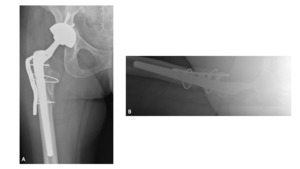

A 63-year-old female presented with recurrent THA instability - verbal consent was obtained for this report. She underwent L2-S1 posterior stabilization with L2-L3 anterior lumbar interbody fusion in May 2002 (Figure 1) and an uncomplicated right THA in April 2007. (Figures 2a-b) Five years following primary THA (July 2011), the patient sustained her first THA dislocation, which was treated with a closed reduction. Between 2011 and 2018, the patient had seven repeat episodes of hip instability – in 2012, one was complicated by a peri-prosthetic femur fracture requiring three revisions and reconstruction with a trochanteric claw plate. She was subsequently diagnosed with a prosthetic joint infection (PJI) which required an antibiotic spacer and subsequent re-implantation three months later. (Figures 3a-b) Following treatment of initial instability and femur fracture, the implants included a size 16 standard taper femoral stem and a 50-mm acetabular shell with 32-mm liner.